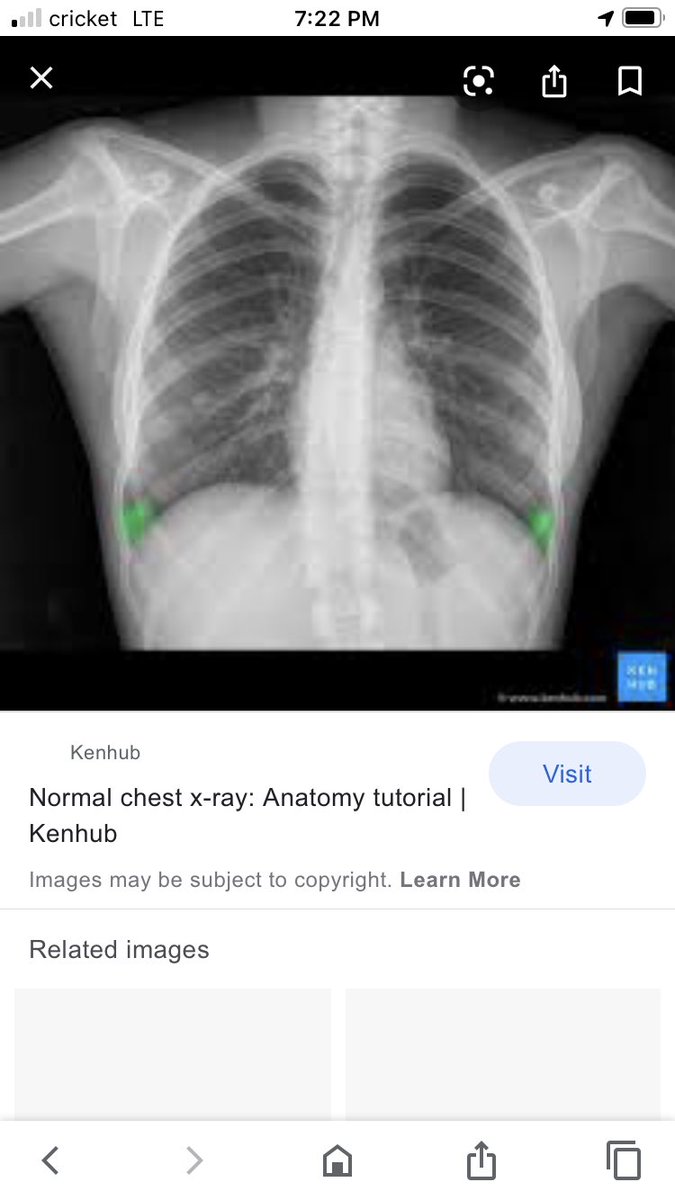

A normal chest X-ray vs a chest X-ray of someone with COVID-19. This is more than just the flu. Pray for us healthcare workers. We are tired and drained and not okay.

IcuGrad's tweet image. A normal chest X-ray vs a chest X-ray of someone with COVID-19.

This is more than just the flu. Pray for us healthcare workers. We are tired and drained and not okay.